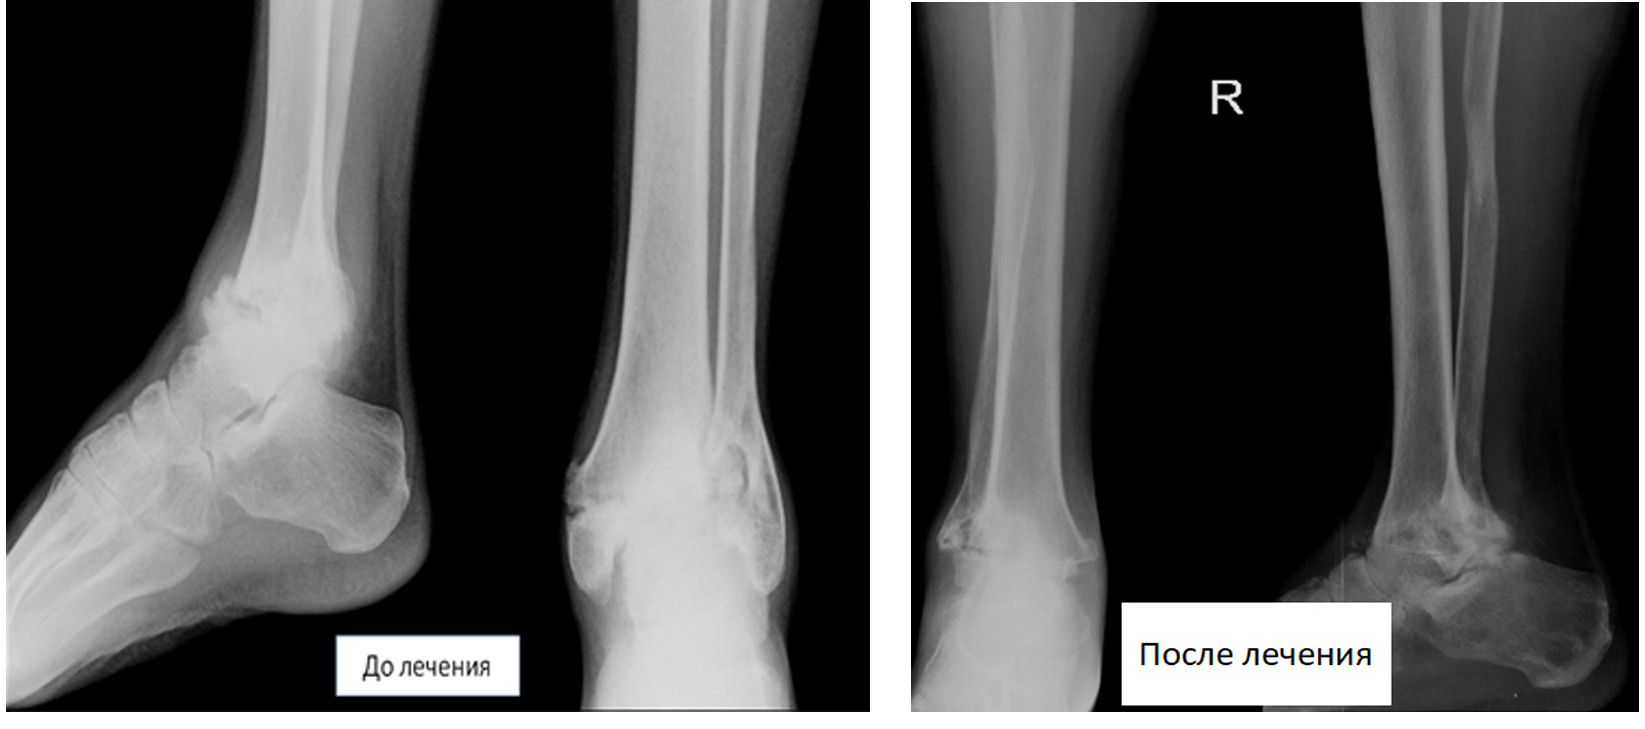

Чоловік звернувся з посттравматичним артрозом правого гомілковоступневого суглоба. До звернення неодноразово лікувався в різних медустановах, де йому проводилося медикаментозне лікування, внутрішньосуглобове введення препаратів гіалуронової кислоти. Після кожного курсу лікування протягом 3-5 місяці біль в області суглоба зменшувалися, а потім знову посилювалися.

При рентгенологічному обстеженні у пацієнта було виявлено повне руйнування гомілковоступневого суглоба. У зв'язку з тривалим неефективним лікуванням і постійними сильними болями пацієнтові в державній лікарні було запропоновано виконати ампутацію на рівні гомілки.

Нами було виконано оперативне лікування, спрямоване на збереження кінцівки. В даний час пацієнт активно користується своєю ногою. Ходить практично не кульгуючи і повернувся до колишньої роботи.